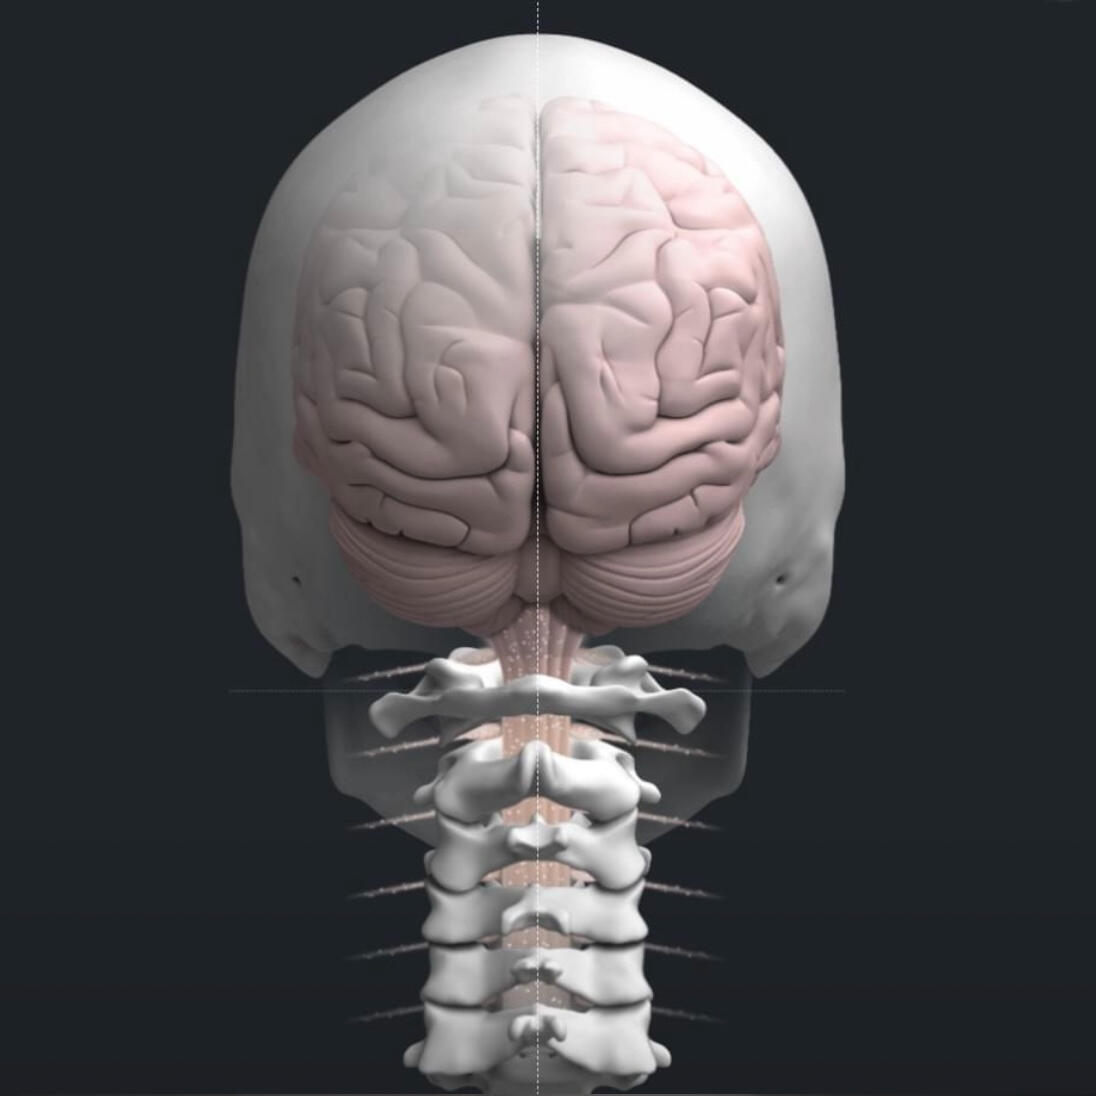

Our chiropractic care focuses on how the brain and nervous system communicate with the body. We use precise, specific adjustments, not force, to support function and healthy adaptation.This approach is gentle and safe for families, children, and athletes alike. The goal is not chasing symptoms, but helping the body change how it adapts and functions over time.

Spinal disc injuries require more than symptom-based care. Our spinal disc rehabilitation approach in Inver Grove Heights focuses on restoring movement, reducing pressure on the disc, and improving how the spine and nervous system work together over time. Care is guided by imaging, clinical findings, and measured progress, not guesswork or force.This care is designed for people dealing with disc herniations, disc bulges, sciatica, chronic back or neck pain, and those who have not improved with traditional chiropractic care. It is also appropriate for individuals looking for non surgical disc care before considering injections or surgery.